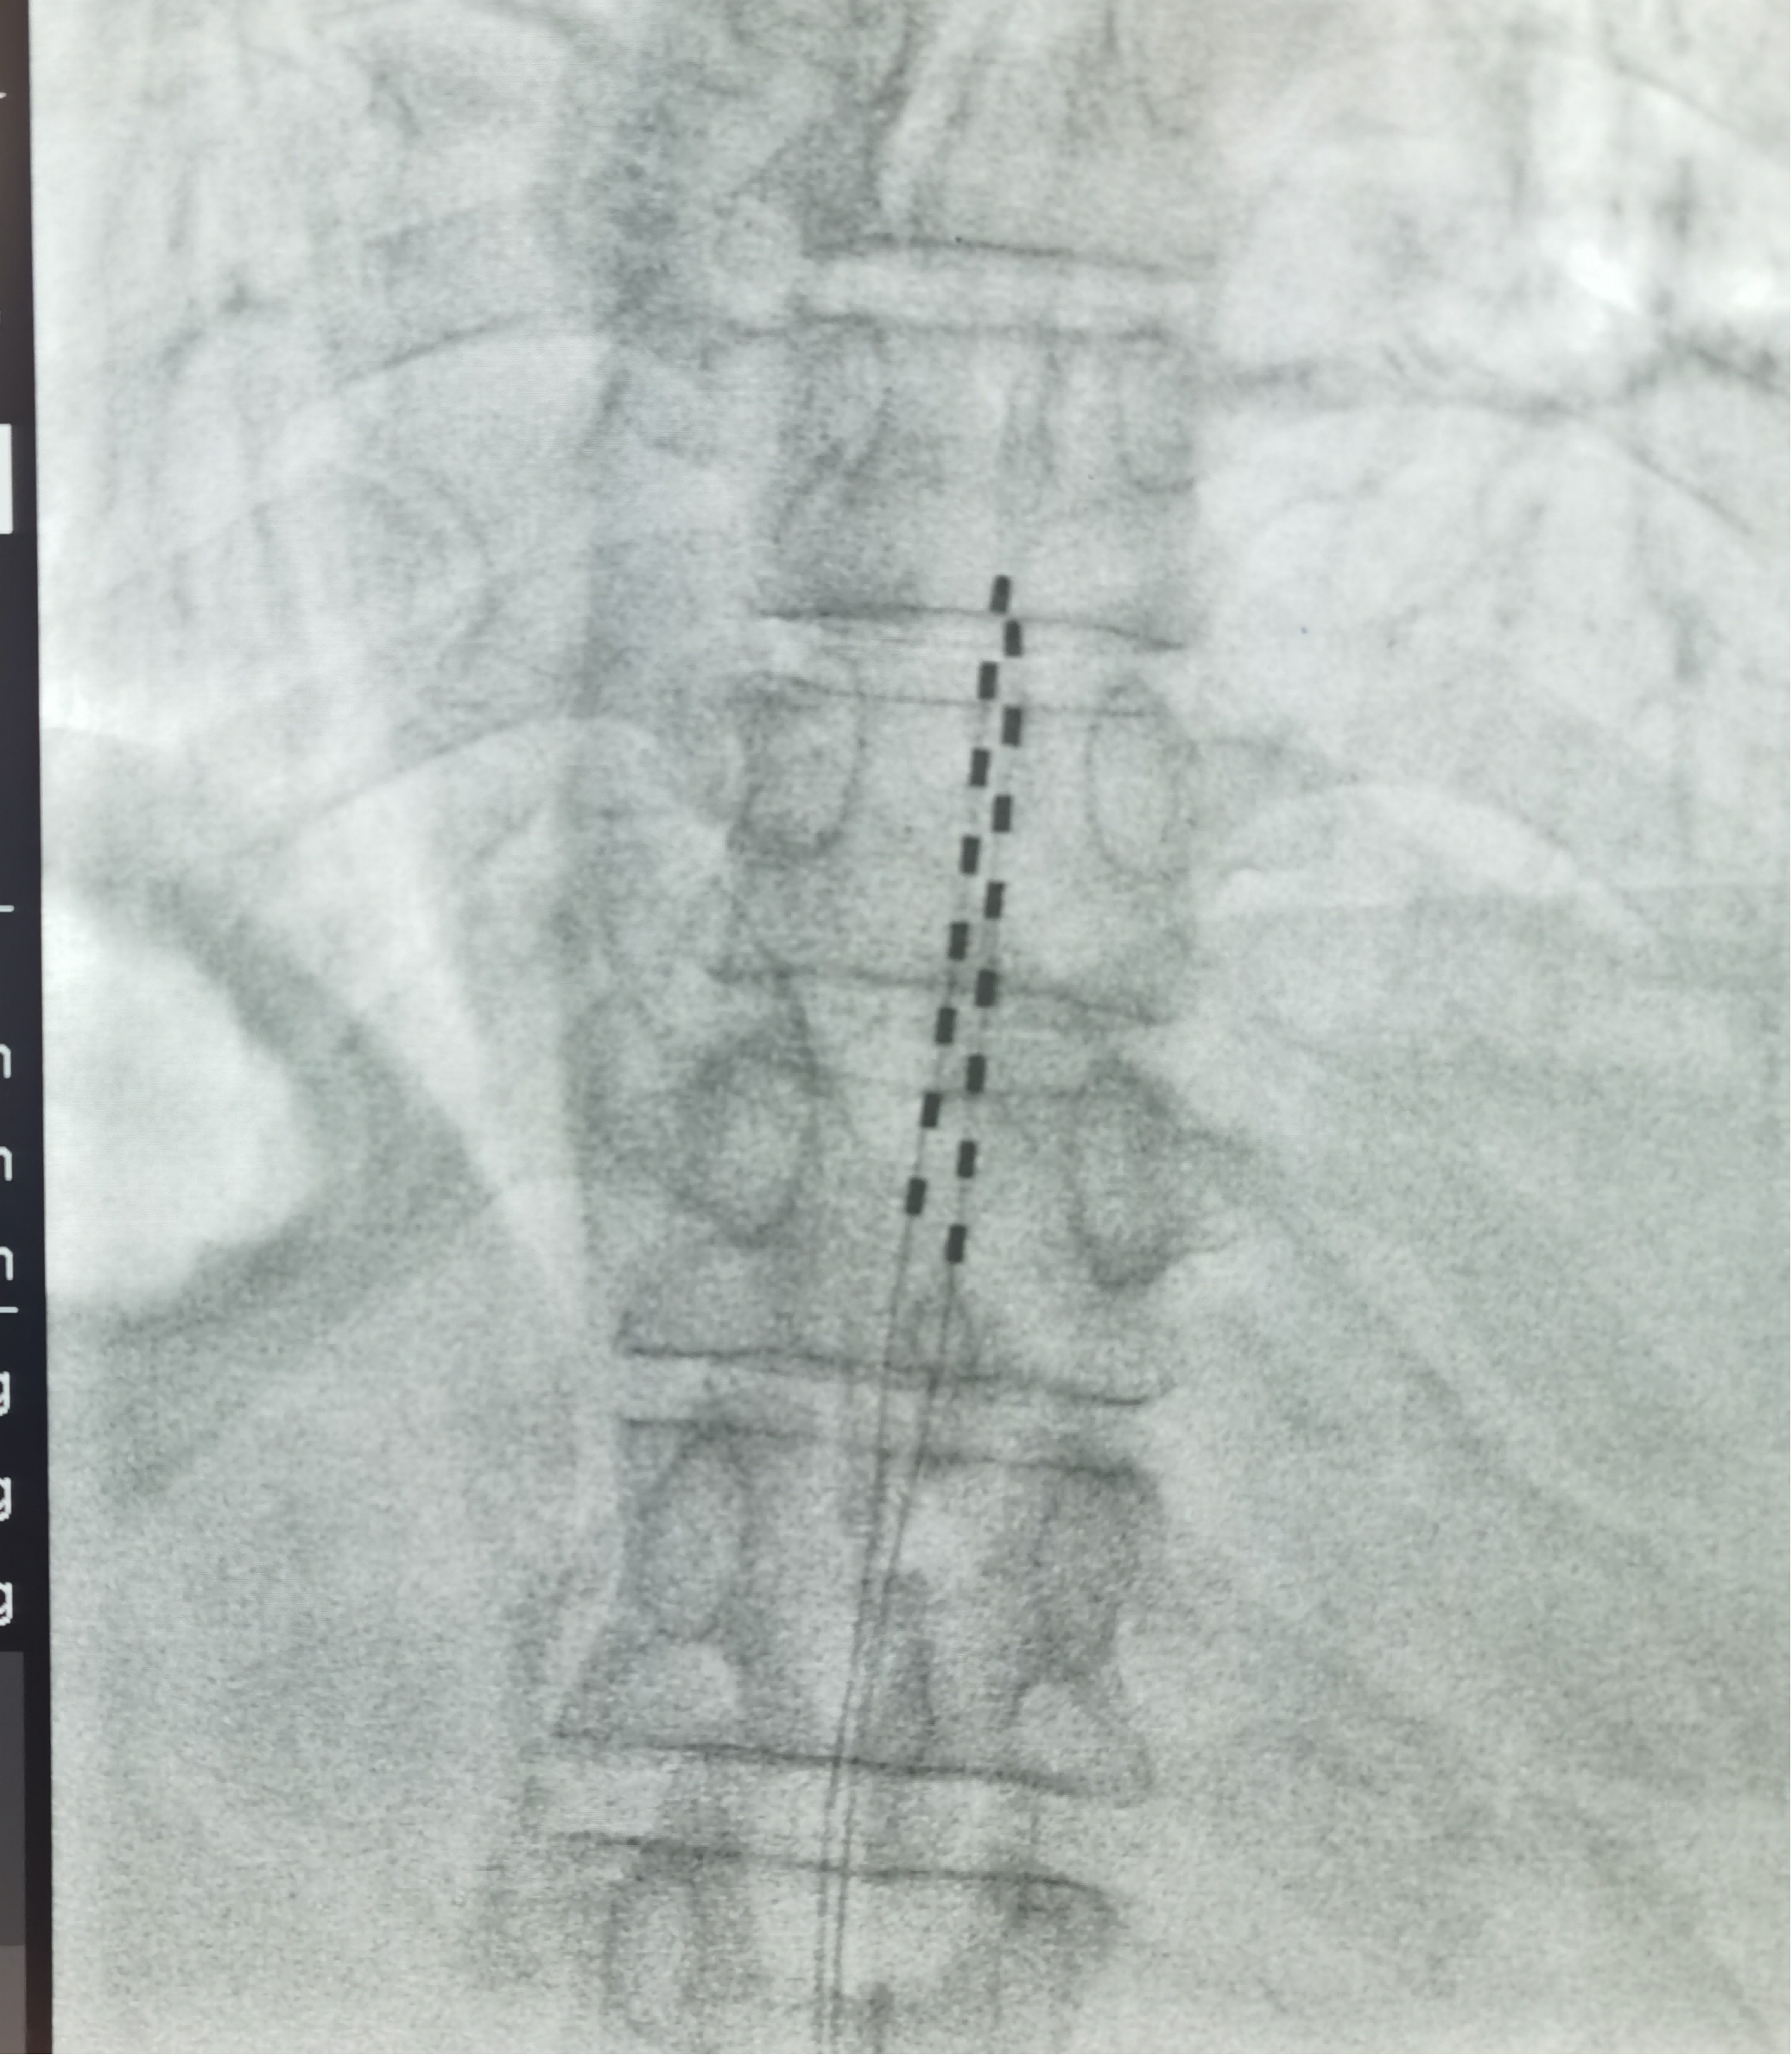

我们可以把受损的神经想象成一个“乱报火警”的系统。而脊髓电刺激技术,是在您的脊髓硬膜外腔植入一根细小的电极,它释放出微弱、舒适的脉冲电流。这种电流可以覆盖并“干扰”原本由受损神经上传到大脑的异常疼痛信号(就像用一段优美的音乐盖过了刺耳的噪音),从而让大脑感知不到疼痛,取而代之的是一种酥麻感。

第一阶段:临时刺激。 我们会在局部麻醉下,为您临时植入电极。您将带着一个体外刺激器回家,治疗10-14天。在这期间,您可以真实地感受疼痛的缓解程度。大约95%的患者能有明显的疼痛缓解,只有极少部分患者效果欠佳,才进入下一步。

第二阶段:永久植入。如果体验治疗效果明确,我们会为您一个小手术,植入永久性的脉冲发生器和电极。整个系统完全植入体内,体外通过遥控器控制,不影响日常生活和沐浴。